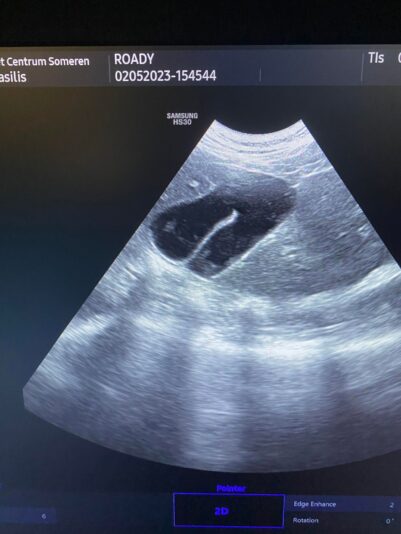

these are the photos of the bloodwork and from the ultrasound

Hi Geert and the whole team,

This post is about a patient of mine that came to me on Wednesday.

General information and history: Cat, male, not castrated, 11 years old with different behaviour since 3 days. According with the owners, the cat didnt want to eat and drink for 3 days. Also he wasnt active and he was hiding. The owners didnt have…